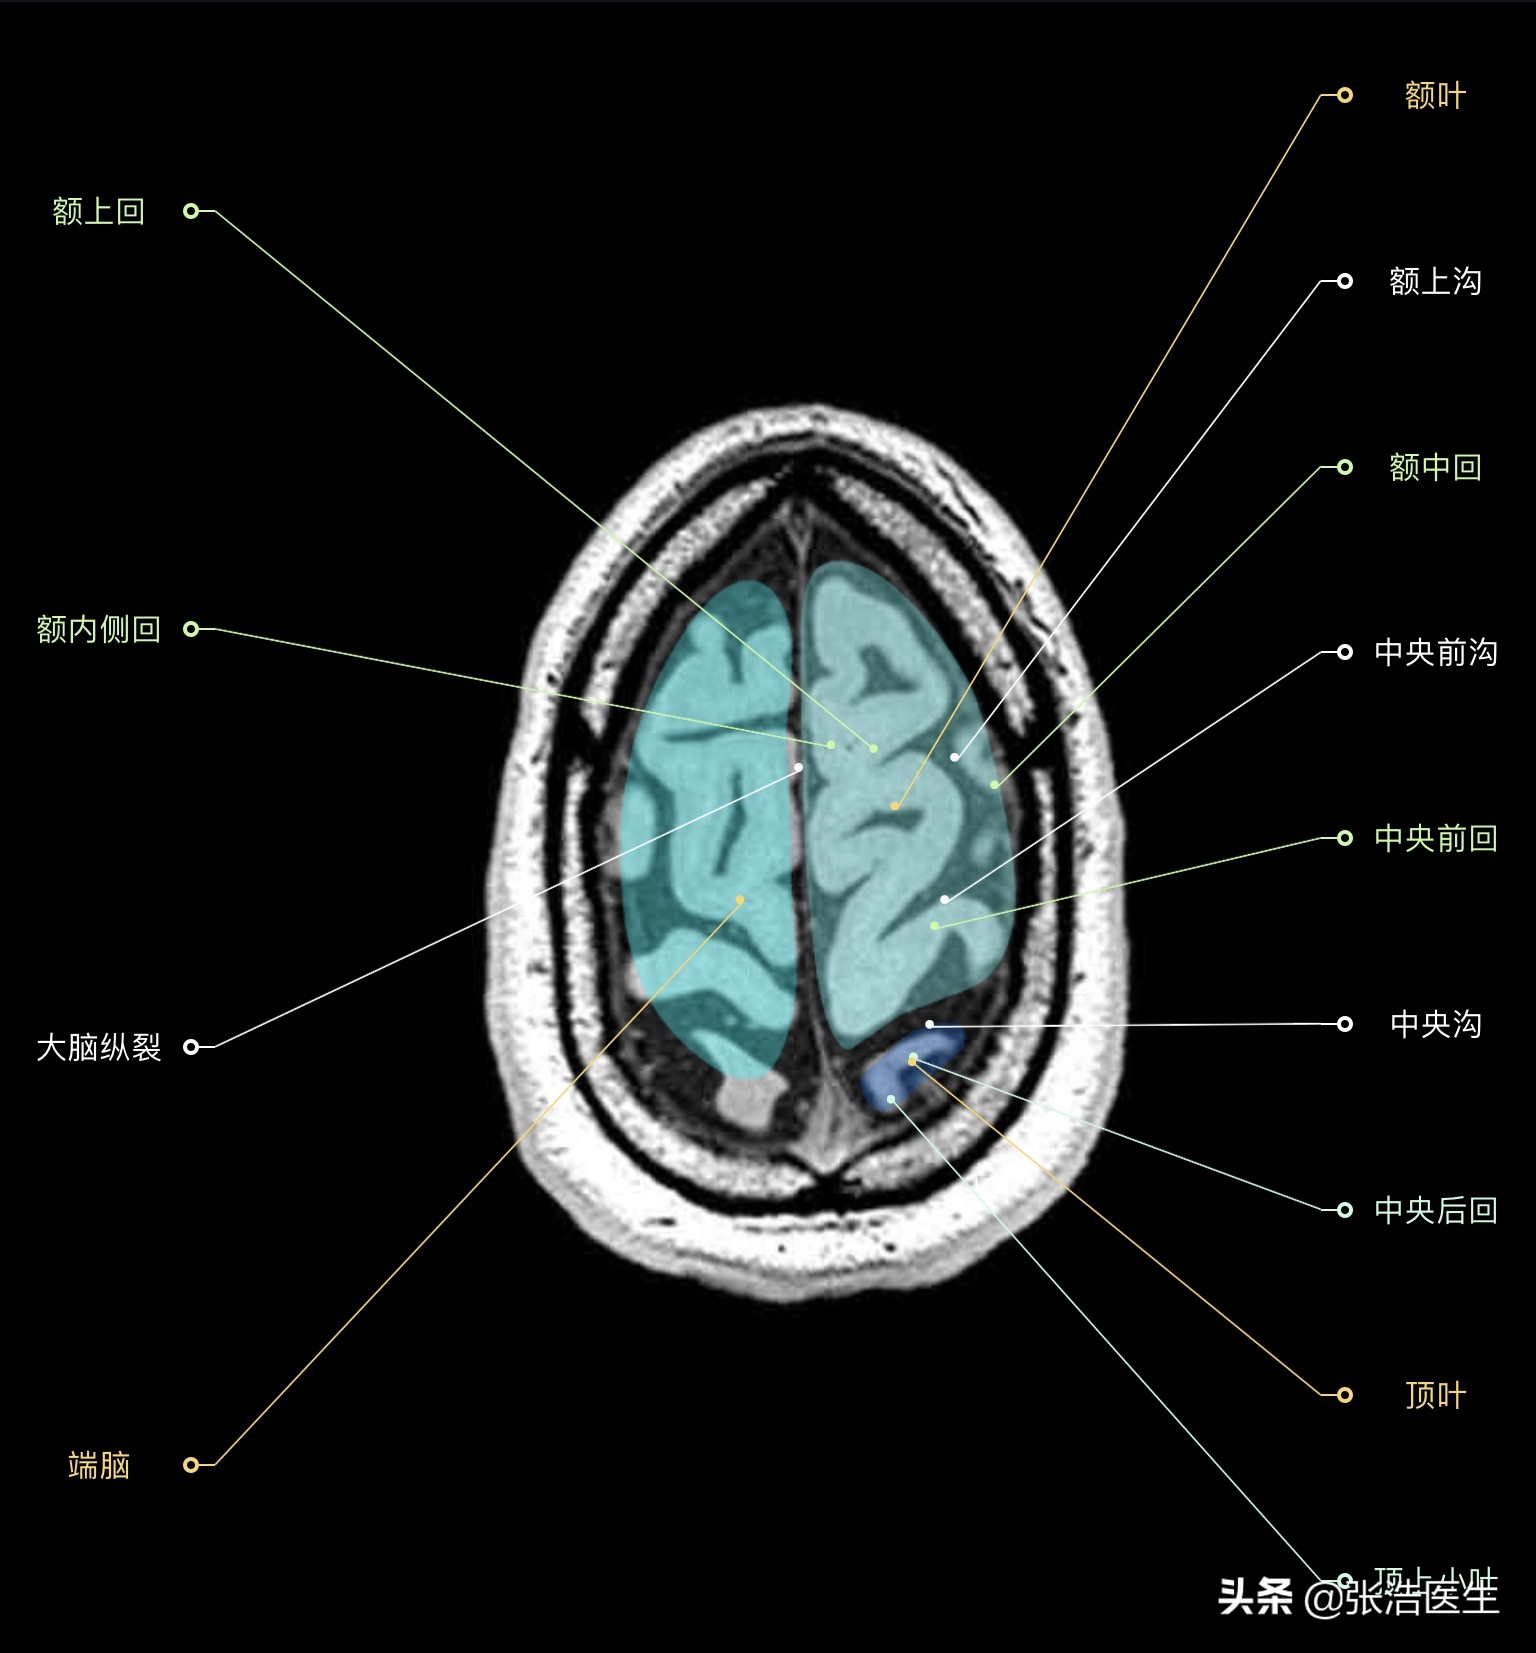

颅脑MRI横断面高清解剖图谱(图层1)